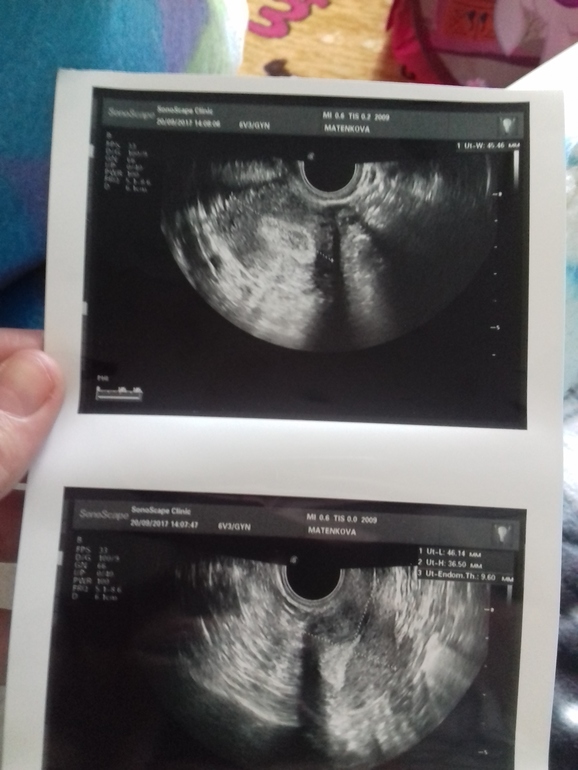

Решила здесь сделать узи малого таза

Но заключение не дали,а в картинках я ничего не понимаю... сказали что сейчас отлично

на картинках замеры яичников и матки, и толщина эндометрия..больше нет? фолликулы не замеряли?

Сказала что все в норме, овуляция была

Видно что лопнул.

судя по всему я здорова))мес были с 2 по 6 сентября